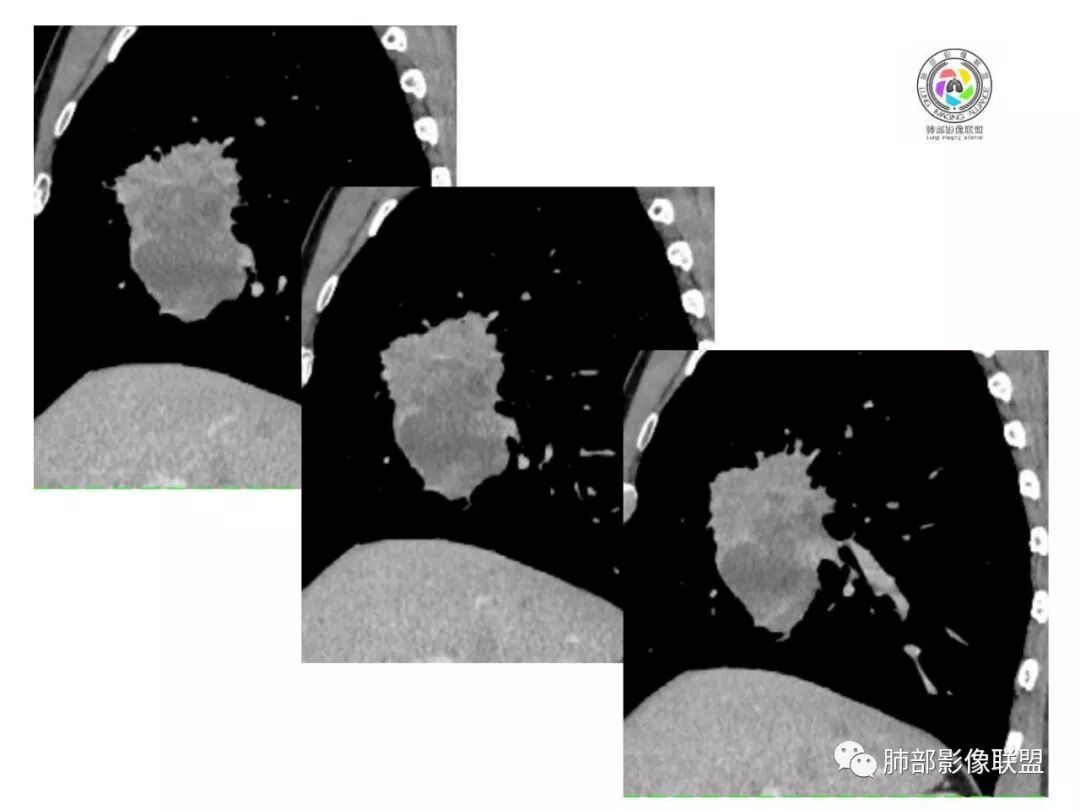

患者中老年男性,体检发现肺部占位。

胸CT:右肺中叶实性占位性病变,呈膨胀性生长,对斜裂明显挤压,右肺中叶外侧段阻塞,并在边缘可见分叶、毛刺、棘突样改变,胸膜牵拉;增强可见病灶明显强化,可见边缘模糊血管影,病灶内可见大片状低密度区,隆突下可见肿大淋巴结。

诊断考虑:恶性病变。

右肺跨上叶与中叶一实性肿块影,中叶外侧段支气管堵塞,肿块有明显分叶、毛刺、棘突样改变,胸膜牵拉,周围有小花小草;增强可见病灶明显强化,病灶内可见大片状低密度区,以外侧为主,隆突下可见肿大淋巴结,恶性,考虑鳞癌可能。

胸CT:右肺中叶团块样实性占位,边缘膨隆,中叶外侧段阻塞,病灶可见深分叶、棘突,胸膜牵拉;增强不均匀强化,可见边缘模糊血管影,病灶内大片状低密度区,纵隔多发肿大淋巴结。

诊断考虑:恶性病变,鳞?大细胞?鉴别:TB